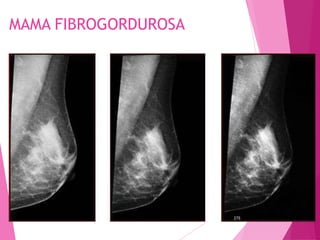

MAMA FIBROGORDUROSA (RADIOLOGICAMENTE

– DENSIDADE MÉDIA):

 50% DE TECIDO ADIPOSO E 50% DE TECIDO

FIBROGLANDULAR;

 DE 30 A 50 ANOS DE IDADE;

 MULHERES JOVENS COM 3 OU MAIS

GESTAÇÕES;

MAMA FIBROGORDUROSA